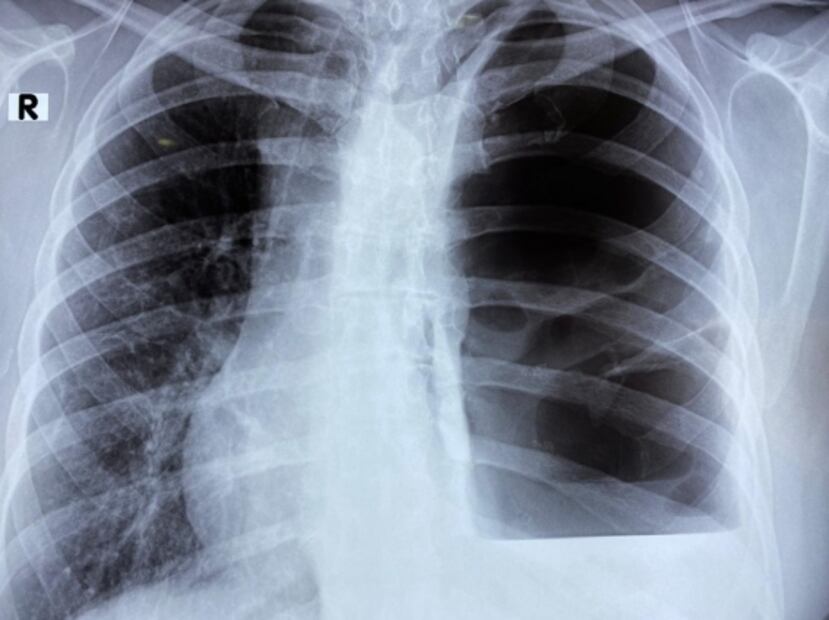

Un científico del Instituto Politécnico Nacional (IPN) destacó la importancia de la atención médica temprana, luego que a través del análisis ha sido posible apreciar cambios pulmonares en pacientes asintomáticos y con pruebas negativas de detección del coronavirus SARS-CoV-2 , que provoca la enfermedad Covid-19 .

Guillermo Prado Villegas señaló a través de un comunicado que es importante, además de la atención médica temprana, contar con estudios de tomografía del tórax, imprescindible para la detección de la enfermedad que ha provocado más de 82 mil fallecimientos en México .

El investigador de la Escuela Superior de Medicina (ESM) reconoció que pese a la negativa que arrojen pruebas de Reacción en Cadena de Polimerasa (PCR), las tomografías son de gran utilidad pues demuestran el daño generado por el coronavirus.

Respecto a las afecciones en personas asintomáticas apuntó que estos pacientes repentinamente presentan dificultad para respirar y en algunos casos fibrosis o necrosis del parénquima pulmonar.

“Hay personas que creen tener un cuadro faríngeo, gripe o tos habitual, cuando realmente cursan con una enfermedad grave y ya tienen neumonía, destrucción del tejido pulmonar, bullas (espacios que carecen de pared epitelial), neumotórax, abscesos o paquipleuritis y diversos grados de fibrosis pulmonar”, puntualizó el experto de la Unidad de Terapia Intensiva Covid del Centro Médico Nacional "La Raza".

Prado Villegas dijo que es importante tratar de forma temprana la neumonía atípica, esto para contener la gravedad de los daños ocasionados por la afección.

"“El uso de esteroides ha mostrado disminución en la morbimortalidad de pacientes con COVID-19, pero es importante recibir terapia pulmonar, la cual debe ir de la mano de broncodilatadores y técnicas de rehabilitación para preservar la mayor cantidad posible de tejido y reducir las secuelas", afirmó.